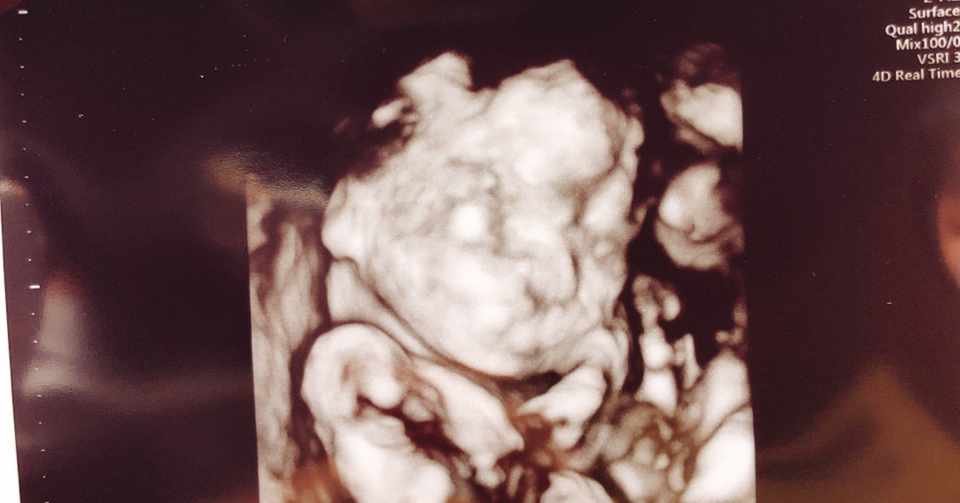

出典:26w1d妊婦健診⑤中期健診(女の子エコー有) この頃になると 女の子の赤ちゃんは、子宮と膀胱が2つの黒い点となって見えます 。.